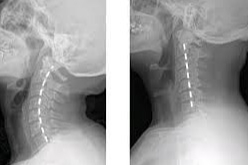

Boyun düzleşmesi, genellikle boyun omurlarının doğal eğrisinin kaybolduğu bir durumu ifade eder. Bu duruma tıp dilinde "boyun düzleşmesi" veya "servikal lordoz kaybı" denir ve çeşitli nedenlerle ortaya çıkabilir. İşte boyun düzleşmesinin başlıca nedenleri:

BOYUN DÜZLEŞMESİNİN BELİRTİLERİ

Boyun Ağrısı: Uzun süreli veya şiddetli ağrı hissi.

Baş Ağrıları: Boyun düzleşmesi, baş ağrılarına yol açabilir.

Sınırlı Hareket Kabiliyeti: Boynun hareketi sınırlı olabilir ve sertleşme hissi yaşanabilir.

Sinir Sıkışması: Kol ve omuzlarda uyuşma veya karıncalanma gibi belirtiler.